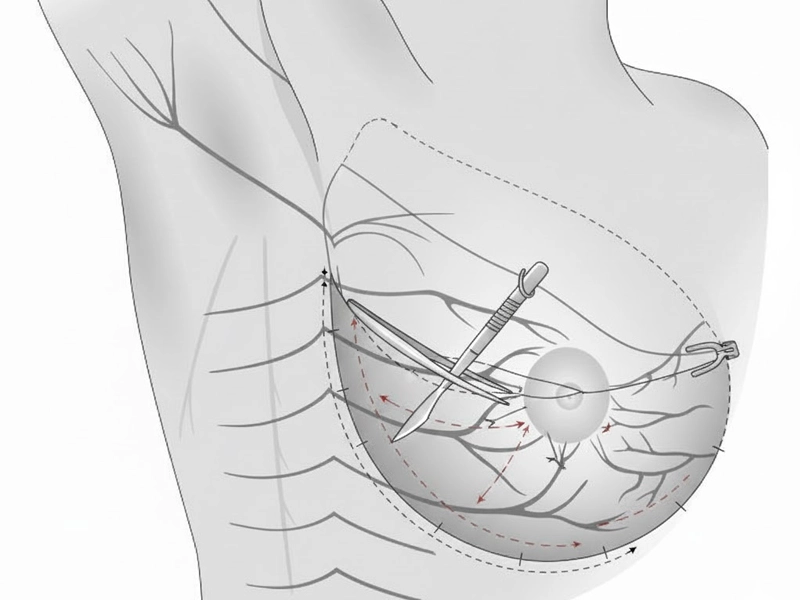

۲) تسلط کامل بر انکوپلاستی (Oncoplastic Breast Surgery)

این یکی از مهمترین مزایای نسل جدید جراحان پستان است:

• ترکیب جراحی سرطان با طراحی دقیق زیبایی

• مهارت در ماموپلاستی درمانی

• بازسازی فوری یا تأخیری بدون نیاز به ایمپلنت

• حداقلسازی اسکار

• راهکارهای حفظ NAC و حفظ فرم طبیعی پستان حتی در جراحیهای گسترده

این سطح از مهارت، جراحی سرطان پستان را از یک عمل صرفاً «حذف توده» به یک عمل بازسازانه، دقیق و هنرمندانه تبدیل کرده است.

۳) توانمندی در بازسازی پستان (Breast Reconstruction)

نسل جدید جراحان پستان، برای بازسازیهای پیچیده آماده شدهاند:

• بازسازی بدون پروتز با استفاده از بافت خود بیمار

• بازسازی با پروتزهای پیشرفته

• اصلاح دفورمیتیهای ناشی از جراحیهای قبلی

• کانتورینگ و بهبود تقارن پس از ماستکتومی